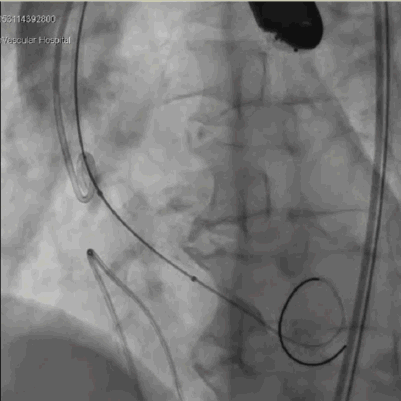

手术过程

主动脉根部造影,冠脉显影良好

右窦中心位 标准位释放瓣膜

人工瓣膜位置、形态良好,无反流

术中,先对人工瓣膜进行定位,到达预期位置后精准释放,手术结果令人满意。